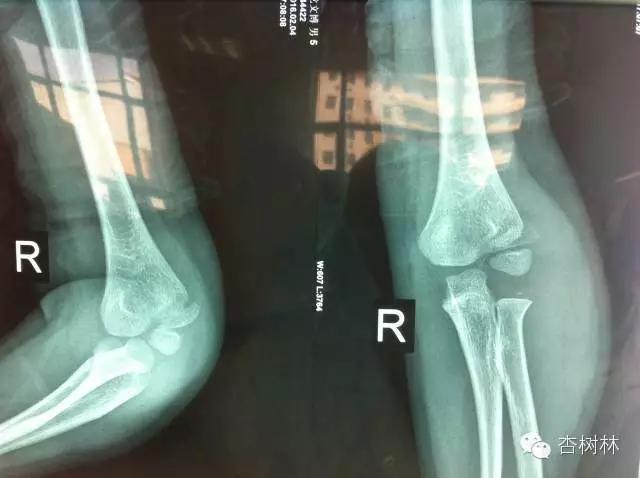

病例讨论问题1:请老师们看看,男孩6岁,外伤后14天,现仍肿胀,功能差,个人认为是肱骨外髁骨折,拟切开复位交叉克氏针固定,可行吗?

TJPO张中礼 : 从正侧位片看,干骺端骨折端移位明显,伴肱骨小头外移外翻,间接判断骨折累及关节面且关节面中断,高度怀疑为关节内骨折。持续伸肌总腱牵拉骨块相关的力学不稳定 骨折端血肿充填关节液浸泡相关的不良愈合环境,如不予处理出现骨折不愈合可能性大,远期进一步继发肘关节外翻及肘关节不稳定等。建议积极手术固定。有条件的话可以术前核磁或术中关节造影进一步确认关节面受累情况。

TJPO张中礼:对于本例,如果只根据平片,我们其实没法肯定骨折线一定累及关节面,更没法客观评估关节面移位程度。就像传统的基于平片Jacob分型一样,其实1型和2型 最大区别在于软骨铰链是否完整,而平片恰恰没法提供足够的依据,更多时候我们只是根据干骺端骨块或肱骨小头移位程度、是否倾斜、骨折线是平行分离还是呈外 宽内窄、以及尺桡骨近端有没有相对外移等,来间接判断软骨部分情况。多数情况下,干骺端移位情况可以反映关节面受累情况。但是,严格说来,对所谓“交界 型”肱骨外髁骨折,只根据平片进行判断,我们其实依据并不充分。